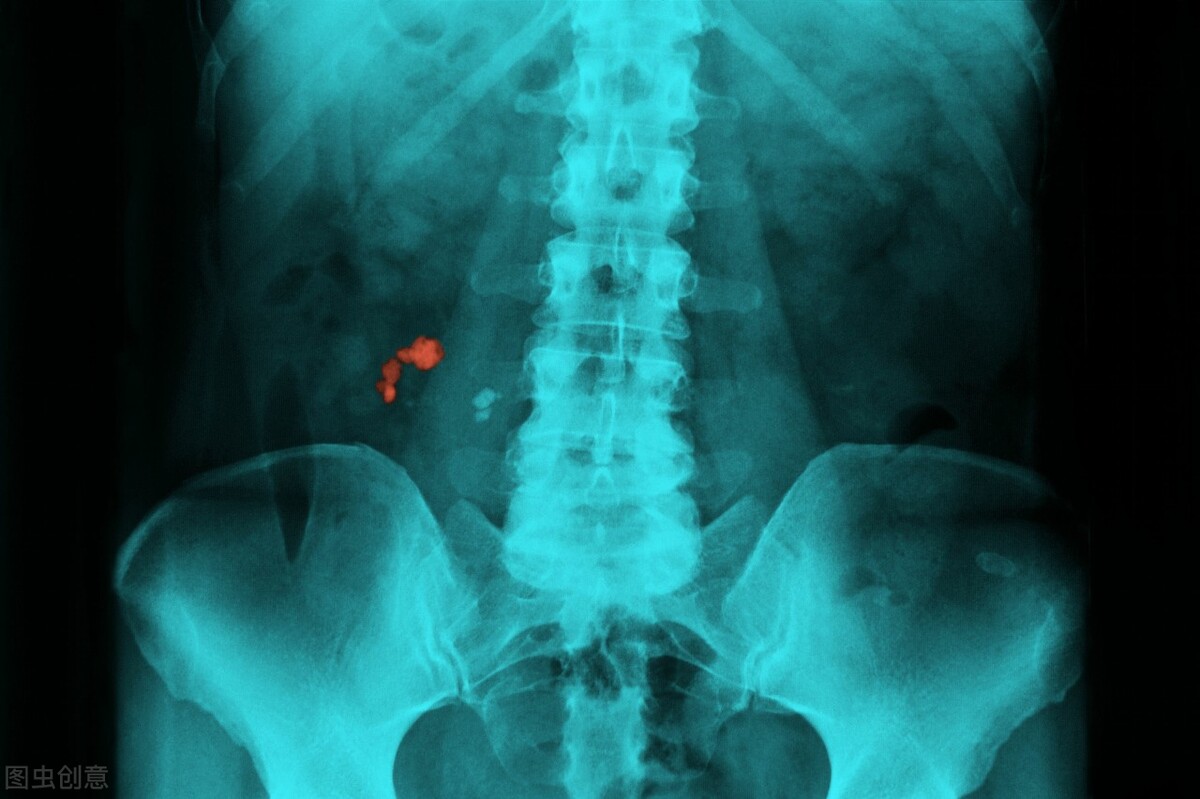

第三种和腰疼有关的肿瘤就是肾细胞癌,这和肾脏所在的位置有关,通常来说肾癌的腰疼是钝痛感,与此同时,还可能会伴随有尿血的出现。